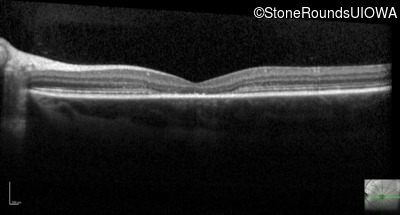

Optical Coherence Tomography - Left - 20/80

Exemplar / OCT Stack